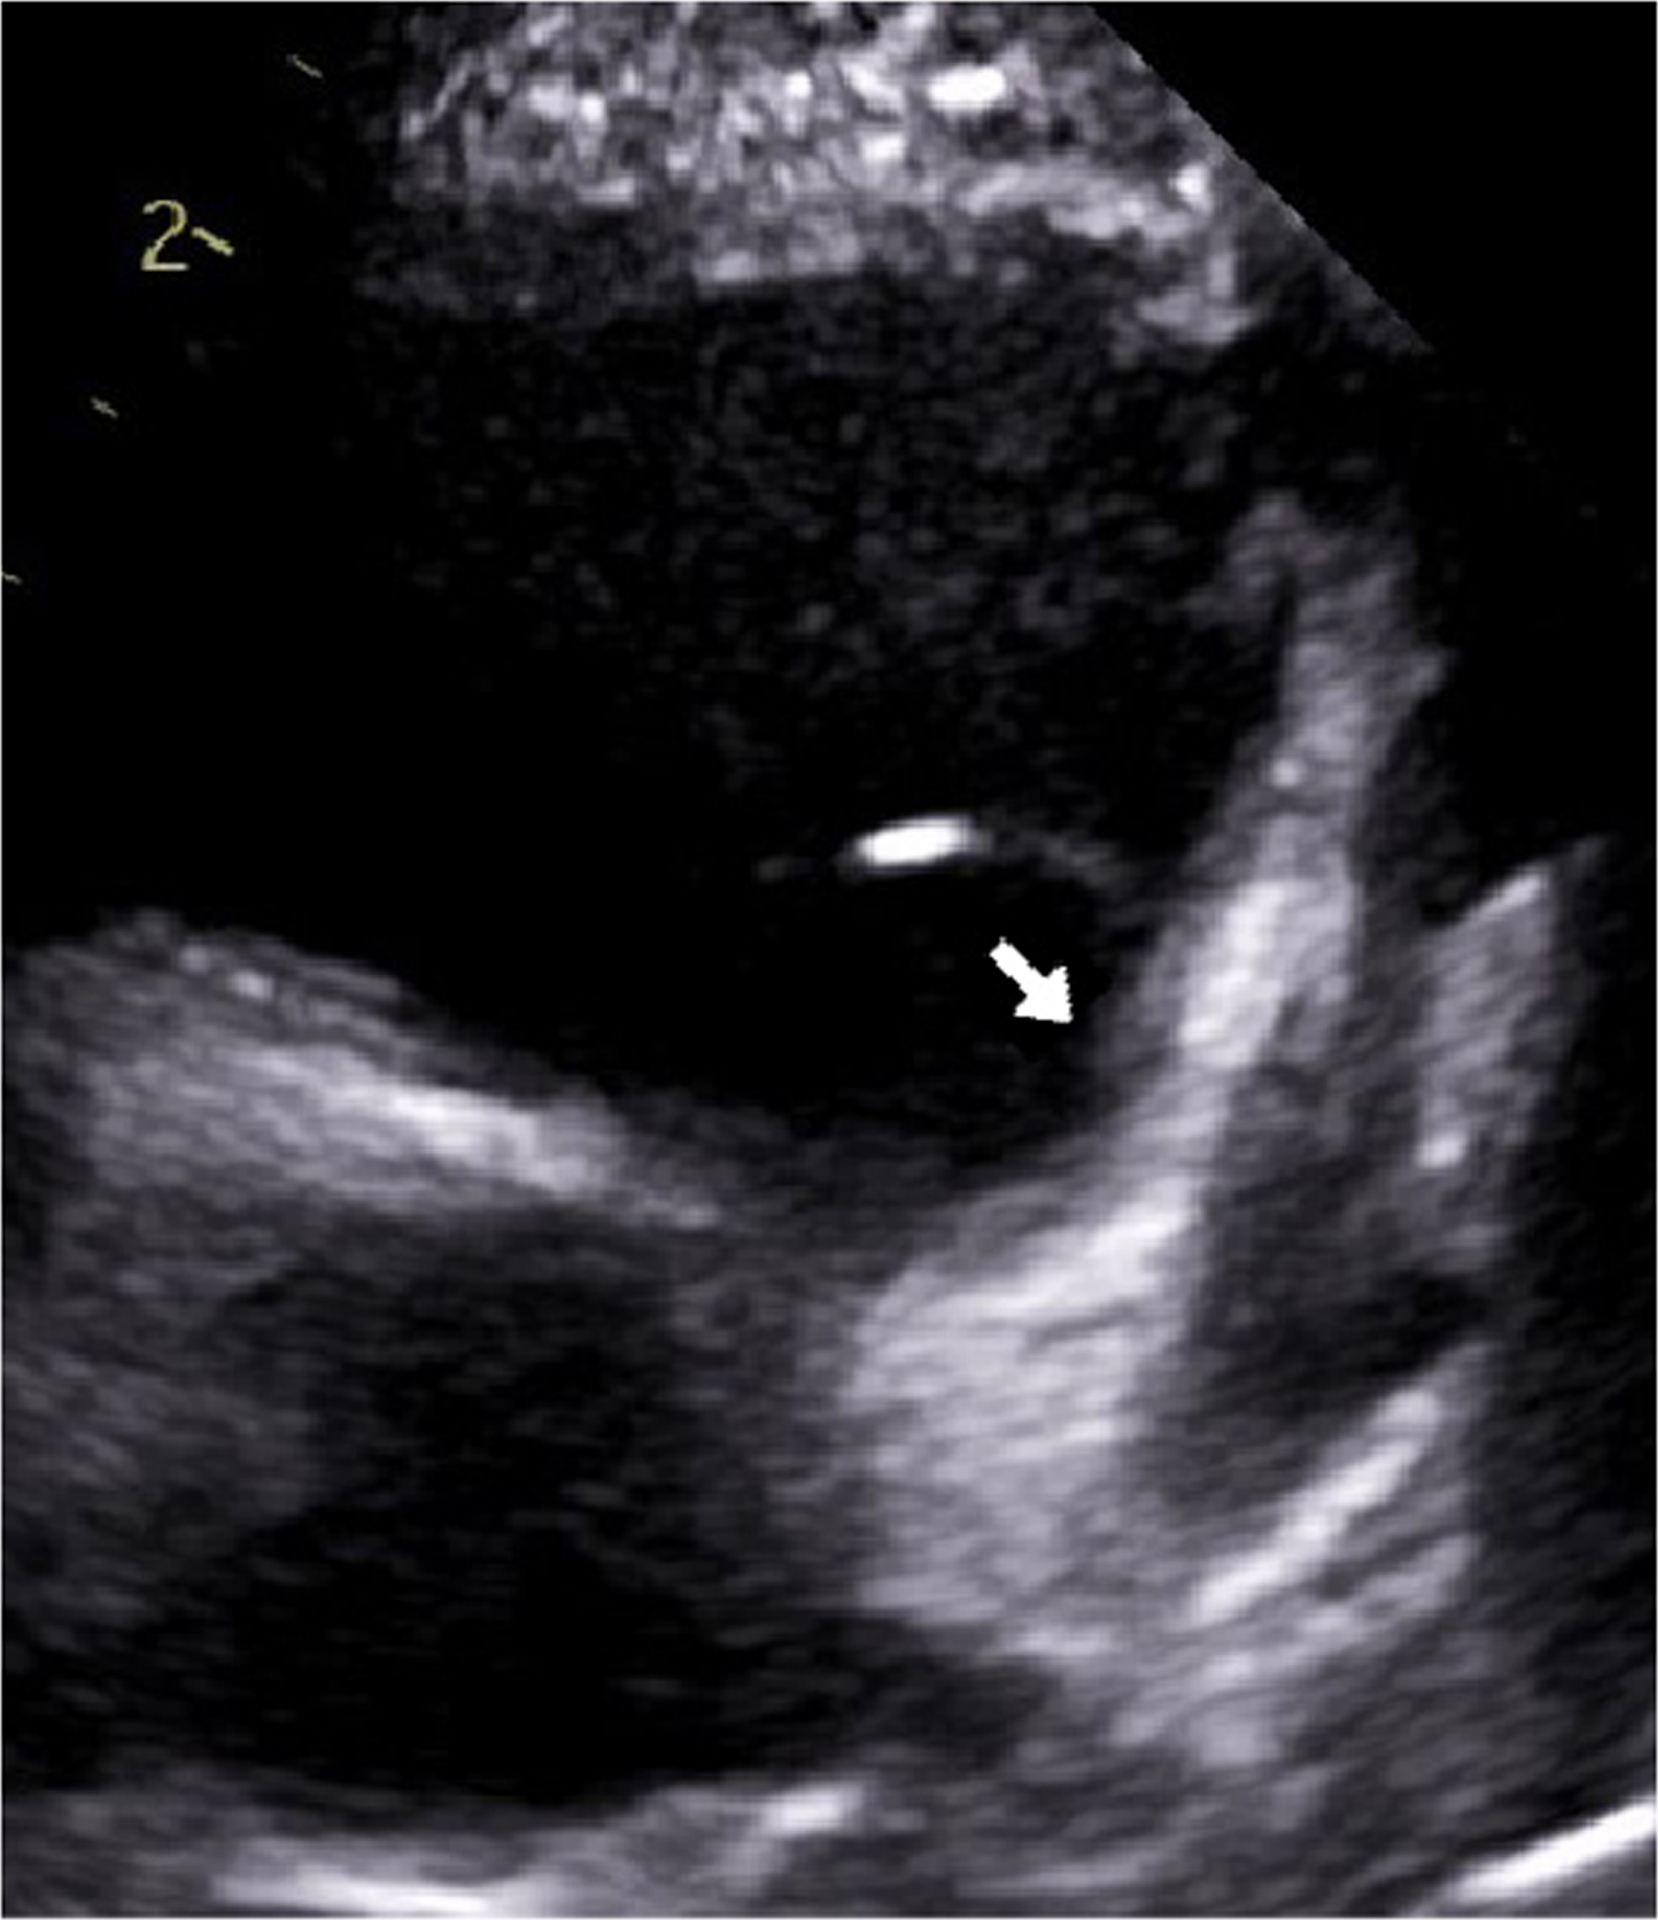

A 5-year-old boy had onset of MIS-C symptoms 55 days after COVID-19 illness and 15 days after receiving his first BNT162b2 COVID-19 vaccination. He was admitted three times for MIS-C, twice after his steroid dose was tapered. On his initial admission, he was given intravenous immunoglobulin (IVIG) and steroids. During his second admission, new, moderate coronary dilation was noted, and he was treated with IVIG and steroids. At his last admission, worsening coronary dilation was noted, and he was treated with infliximab and steroids. During follow-up, he had improvement in his coronary artery dilatation. However, his inflammatory markers increased after steroid wean, and his steroid taper was further extended, after which time his inflammatory markers improved. This is the only such reported case of a patient who was admitted three times for MIS-C complications after Covid-19 vaccination.